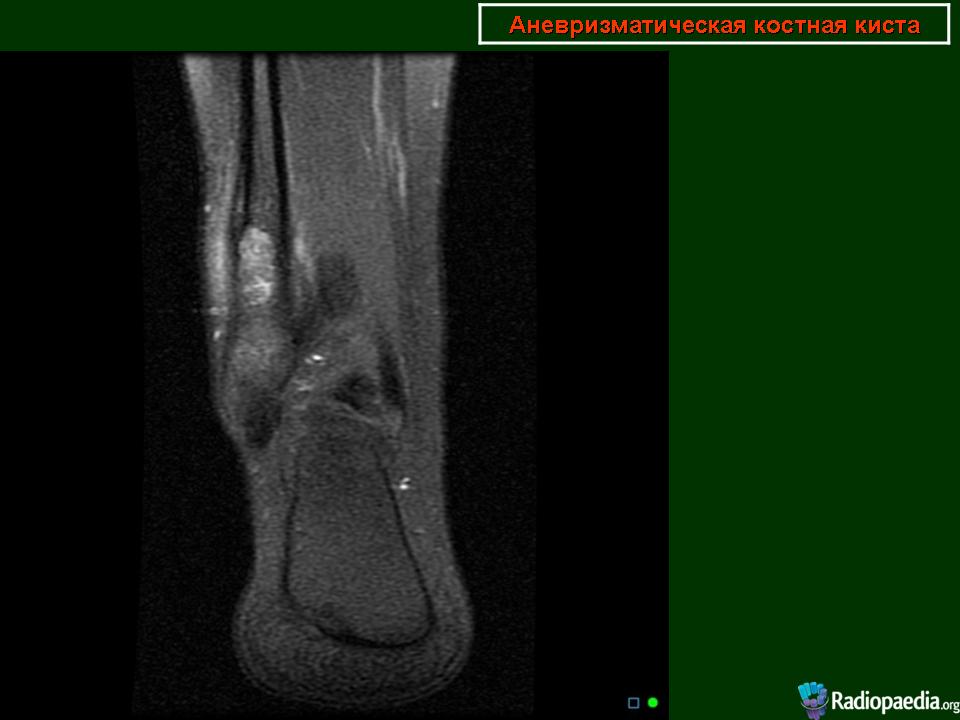

Мужчина с жалобами на периодические боли в голеностопном суставе.Спортсмен.Проходил КТ-исследование 2 года назад в Корее, принес снимки, но заключение письменного почему-то не получил.На словах сказали, что "какая-то опухоль".Его родственник -мой коллега_ попросил провести рентгенографию сустава, после чего направил на МРТ.Рентгенограммы по тех. причинам буду чуть позже))))

По поводу случая-пока склоняюсь к аневризматической костной кисте.Может быть и неправа, но узнаю результаты похода пациента в онкодиспансер.

Я за кисту. Но на МРТ не нравиться , что процесс выходит за пределы кости.